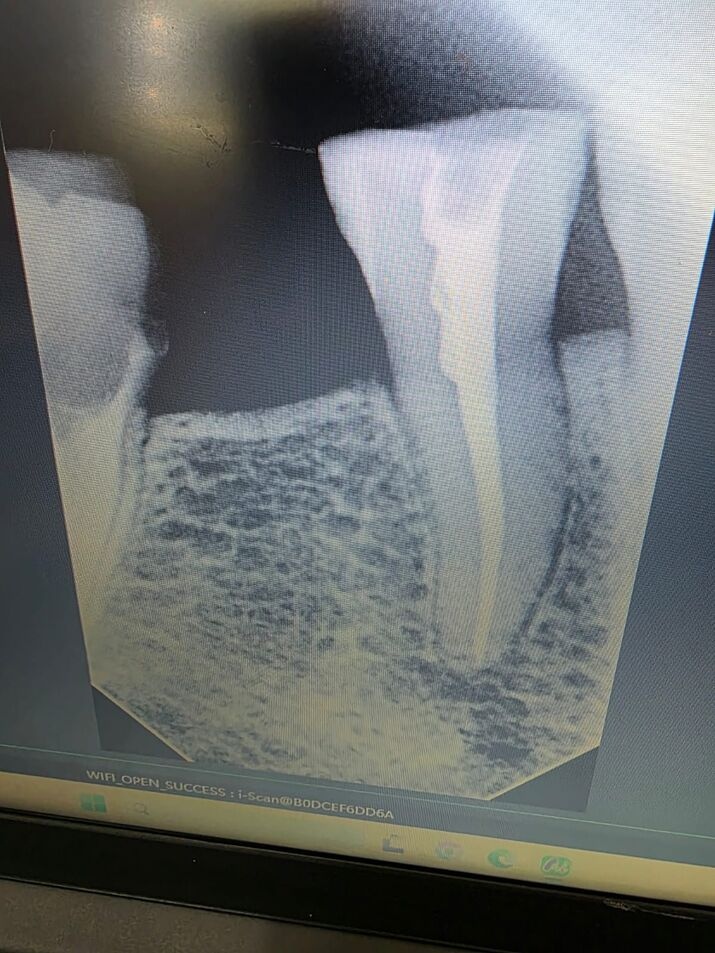

Dental X-Rays are a vital diagnostic tool that allows dentists to see issues that are not visible during a regular examination. At Om Kapan Dental, we use modern digital X-ray technology to identify cavities, impacted teeth, bone loss, infections, and other underlying dental problems. This precise information ensures that each patient receives an accurate diagnosis and an effective treatment plan.

Our digital X-rays are fast, safe, and provide high-quality images with minimal radiation exposure. By combining X-ray findings with a dental examination, our team can detect dental issues early, preventing complex treatments in the future and helping you maintain strong, healthy teeth and gums.